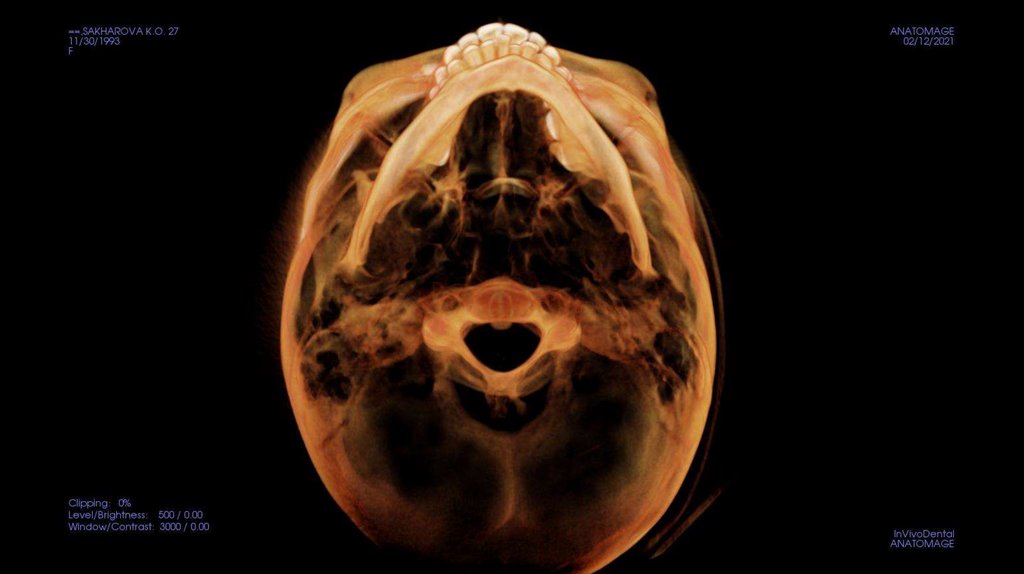

По рассчетам снимков:

• Ретрузия резцов верхней челюсти

• Компрессия головок суставов, особенно правого( началось

ремоделирование)

• Костная ассиметрия(10 мм)

• 2 класс

• 25, 46 зуб – нуждается в санации

• Требуется профессиональняа гигиена полости рта

• Клиновидные дефекты 43, 44

• 18, 28, 38, 48 отсутствуют.

Скелетный: II класс.